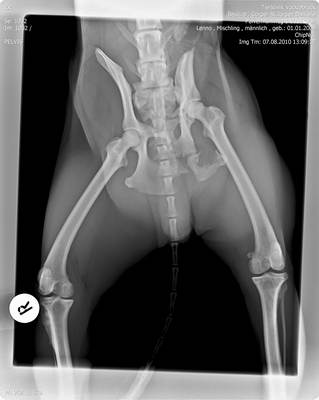

Ich bin mit ihm am Sonntag, den 08.08.2010 nach Wien in die Tierklinik Breitensee gefahren und dort wurde er sofort stationär aufgenommen. In der Nacht von Dienstag auf Mittwoch wurde er operiert – 5 Stunden hat die OP gedauert.

Die Kontrolle am 21.08.2010 verlief nicht so gut, leider hat sich auf der rechten Seite etwas verschoben sodass wir am 26.08.2010 nochmals zur Kontrolle nach Wien fahren müssen. Dann ist auch Frau Dr. Rössel anwesend und wir werden besprechen, was wir machen.

Bei der Kontrolle am 26.08.2010 musste Frau Dr. Rössel Leno noch ein mal operieren. Sie hat ihm die beiden Stifte links hinten entfernt, da er bei der Untersuchung große Schmerzen in diesem Bereich gezeigt hat. Die OP war aber kurz und wir konnten schnell wieder nach Hause fahren.